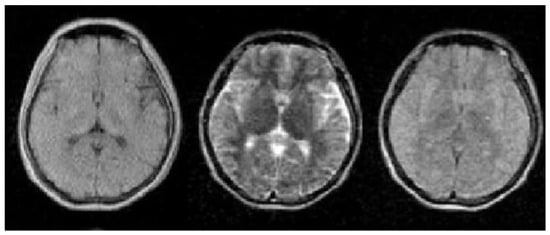

4.2.2. Multimodal Feature Fusion

In medical imaging, different MRI modes are usually used to add more hierarchical features. Taking brain segmentation research as an example, as shown in Figure 9, T1-weighted images can produce good contrast between gray matter and white matter, while T2-weighted images can help to visualize abnormal tissue lesions. FLAIR sequences can more sensitively detect lesions near the brain tissue CSF junction. Therefore, it is very important to consider multidimensional image information to obtain accurate diagnosis results. Xiao et al. [75] took U-Net as the main framework, extracted multiscale features of different modes, fused multimodal features at the decision-making level, and used MRI images of the liver from the McGill University Health Center to build a dataset, with a segmentation accuracy of 81.98%. Zhao et al. [45] proposed a multimodal segmentation network based on a 3D FCN. The network uses two independent V-Net architectures to extract high-dimensional features from PET and CT images with a segmentation accuracy of 89.10%.

Figure 9.

The features of medical images in different dimensions. The left side is the T1-weighted image, the middle is the T2-weighted image, and the right side is the FLAIR-weighted image. It can be seen that images in various dimensions provide different features.